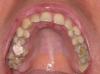

persona Опубликовано 12 октября, 2008 Поделиться Опубликовано 12 октября, 2008 (изменено) Здравствуйте.Хочу спросить совета у специалистов.Мне 25 лет. Решил разобраться со своими кривыми зубами. Пытался и раньше, но то, что мне сделали с помощью обычной пластинки еще в школьные годы, уже давно разъехалось в разные стороны. Мой случай в чем то, наверное, похож на вот этот:http://forum.stom.ru/index.php?showtopic=3286, только у меня все еще более запущено.Основная проблема в том, что у меня не вырос левый клык. Он остался внутри и лежит горизонтально. В результате, все верхние резцы съехали на свободное место, появились большие щели. Левая двойка даже умудрилась заехать за нижний клык. На нижней челюсти зубы скученны, что конечно тоже хотелось бы исправить. Был у разных врачей. Насколько я понял, в моем случае желательно использовать брэкеты Damon. Предлагают две стратегии лечения:1) Освобождать место в зоне невышедшего клыка, а затем либо вытягивать его (что маловероятно), либо удалять клык и вставлять имплант на это место. При этом верхние резцы выдвинутся немного вперед и, соответственно, освободится место для выправления нижних зубов без удаления.2) Невышедший клык не трогаем, на его место смещается 4-ка, которая и будет исполнять роль этого клыка. Верхние зубы смещаются к центру, а нижние выпрямляются с удалением левой 4-ки. Последний из посещенных мною врачей как раз предлагает 2-ой подход, а про 1-ый говорит, что на такое лечение уйдет больше времени + придется удалять невышедший клык, без чего можно вполне обойтись + с недоверием относится к выдвижению верхних зубов + наверняка придется удалять какие-то 8-ки + выглядеть все в итоге будет примерно также. Но врач, который предлагал 1-ый способ, тоже вроде опытный специалист, так что я не знаю, кому из них больше доверять. Прошу знающих людей помочь мне определиться с методом лечения, да и вообще поделиться какими-то своими соображениями по поводу моего случая. Выкладываю фотографии и панорамный снимок. На фото верхней челюсти не жвачка , а временная пломба - сейчас как раз прохожу лечение у стоматолога, так что не обращайте внимание. Изменено 12 октября, 2008 пользователем persona Ссылка на комментарий